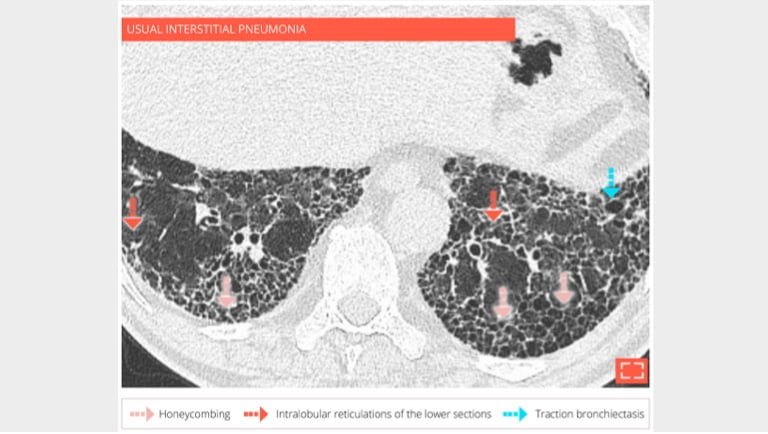

2. Honeycombing

honey-2

69-year-old man with usual interstitial pneumonia. Subpleural honey combing is associated with reticular pattern.